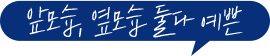

확실한 정면축소 효과! 아이디 윤곽2종

id 윤곽2종 299만원

아이디 윤곽2종

정면 · 측면 어디서봐도 매끄럽게 예뻐지고

뼈까지 예뻐지는 id 윤곽2종 ♥

id 윤곽2종